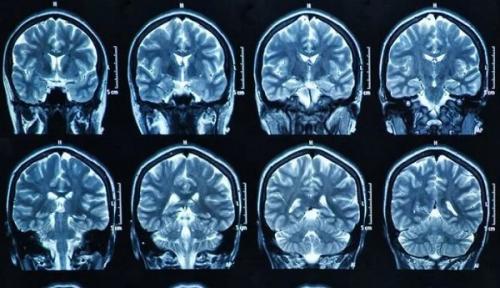

Магнитно-резонансная томография представляет собой экстренный способ диагностики нарушения мозгового кровотока. Инсульт на МРТ головного мозга виден в первые же сутки после развития патологического процесса. Но для его выявления может потребоваться модификация метода, а не стандартная обзорная томография. МРТ после инсульта также проводится. Томография показывает степень нарушения кровотока, поражения тканей. Все же есть отдельные нюансы проведения магнитно-резонансной томографии при подозрениях на инсульт.

Какое МРТ делать после инсульта?

Томография при инсульте проводится двумя основными способами.

- Первый — стандартная обзорная томография. Долгие годы она была единственным вариантом диагностики патологического процесса. Благодаря нейровизуализации врачи получают возможность оценить состояние головного мозга, его отдельных участков. Области ишемии или геморрагии хорошо видны. Можно оценить степень нарушения, спрогнозировать вероятный исход, разработать метод грамотной терапии в определенном клиническом случае. У методики есть минус — она показывает состояние церебральных структур, выявляет патологический процесс только спустя как минимум сутки от развития расстройства. Для экстренного определения нарушения она не годится. Нужна более чувствительная методика.

- Второй — диффузионная МРТ. Эта модификация классического способа должна установить диагноз в первые 24 часа после наступления поражения церебральных структур. Томографический способ основан на способности МРТ-аппарата регистрировать особенности движения молекул воды в нервных тканях. Благодаря чему врачи получают возможность выявить область нарушения работы ЦНС, степень поражения в острейшем периоде.